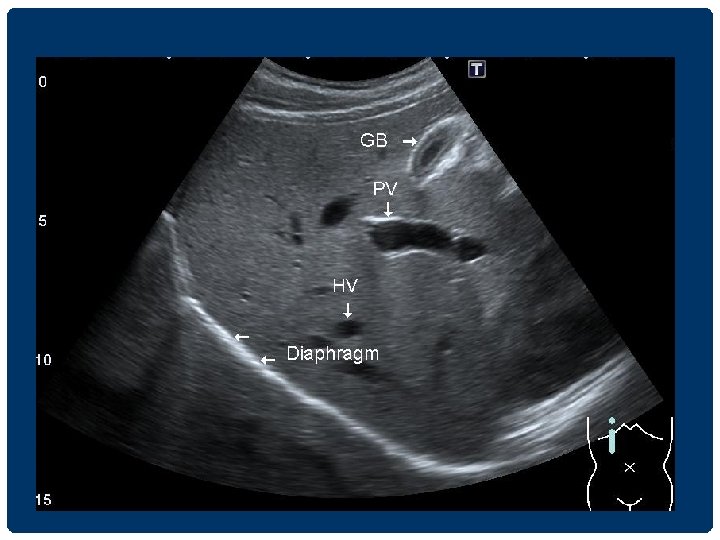

GALLBLADDER GB PV

THE GALLBLADDER GB PV